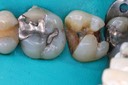

Bryan Sato #2 pre-op

Bryan Sato #2 amalgam removal